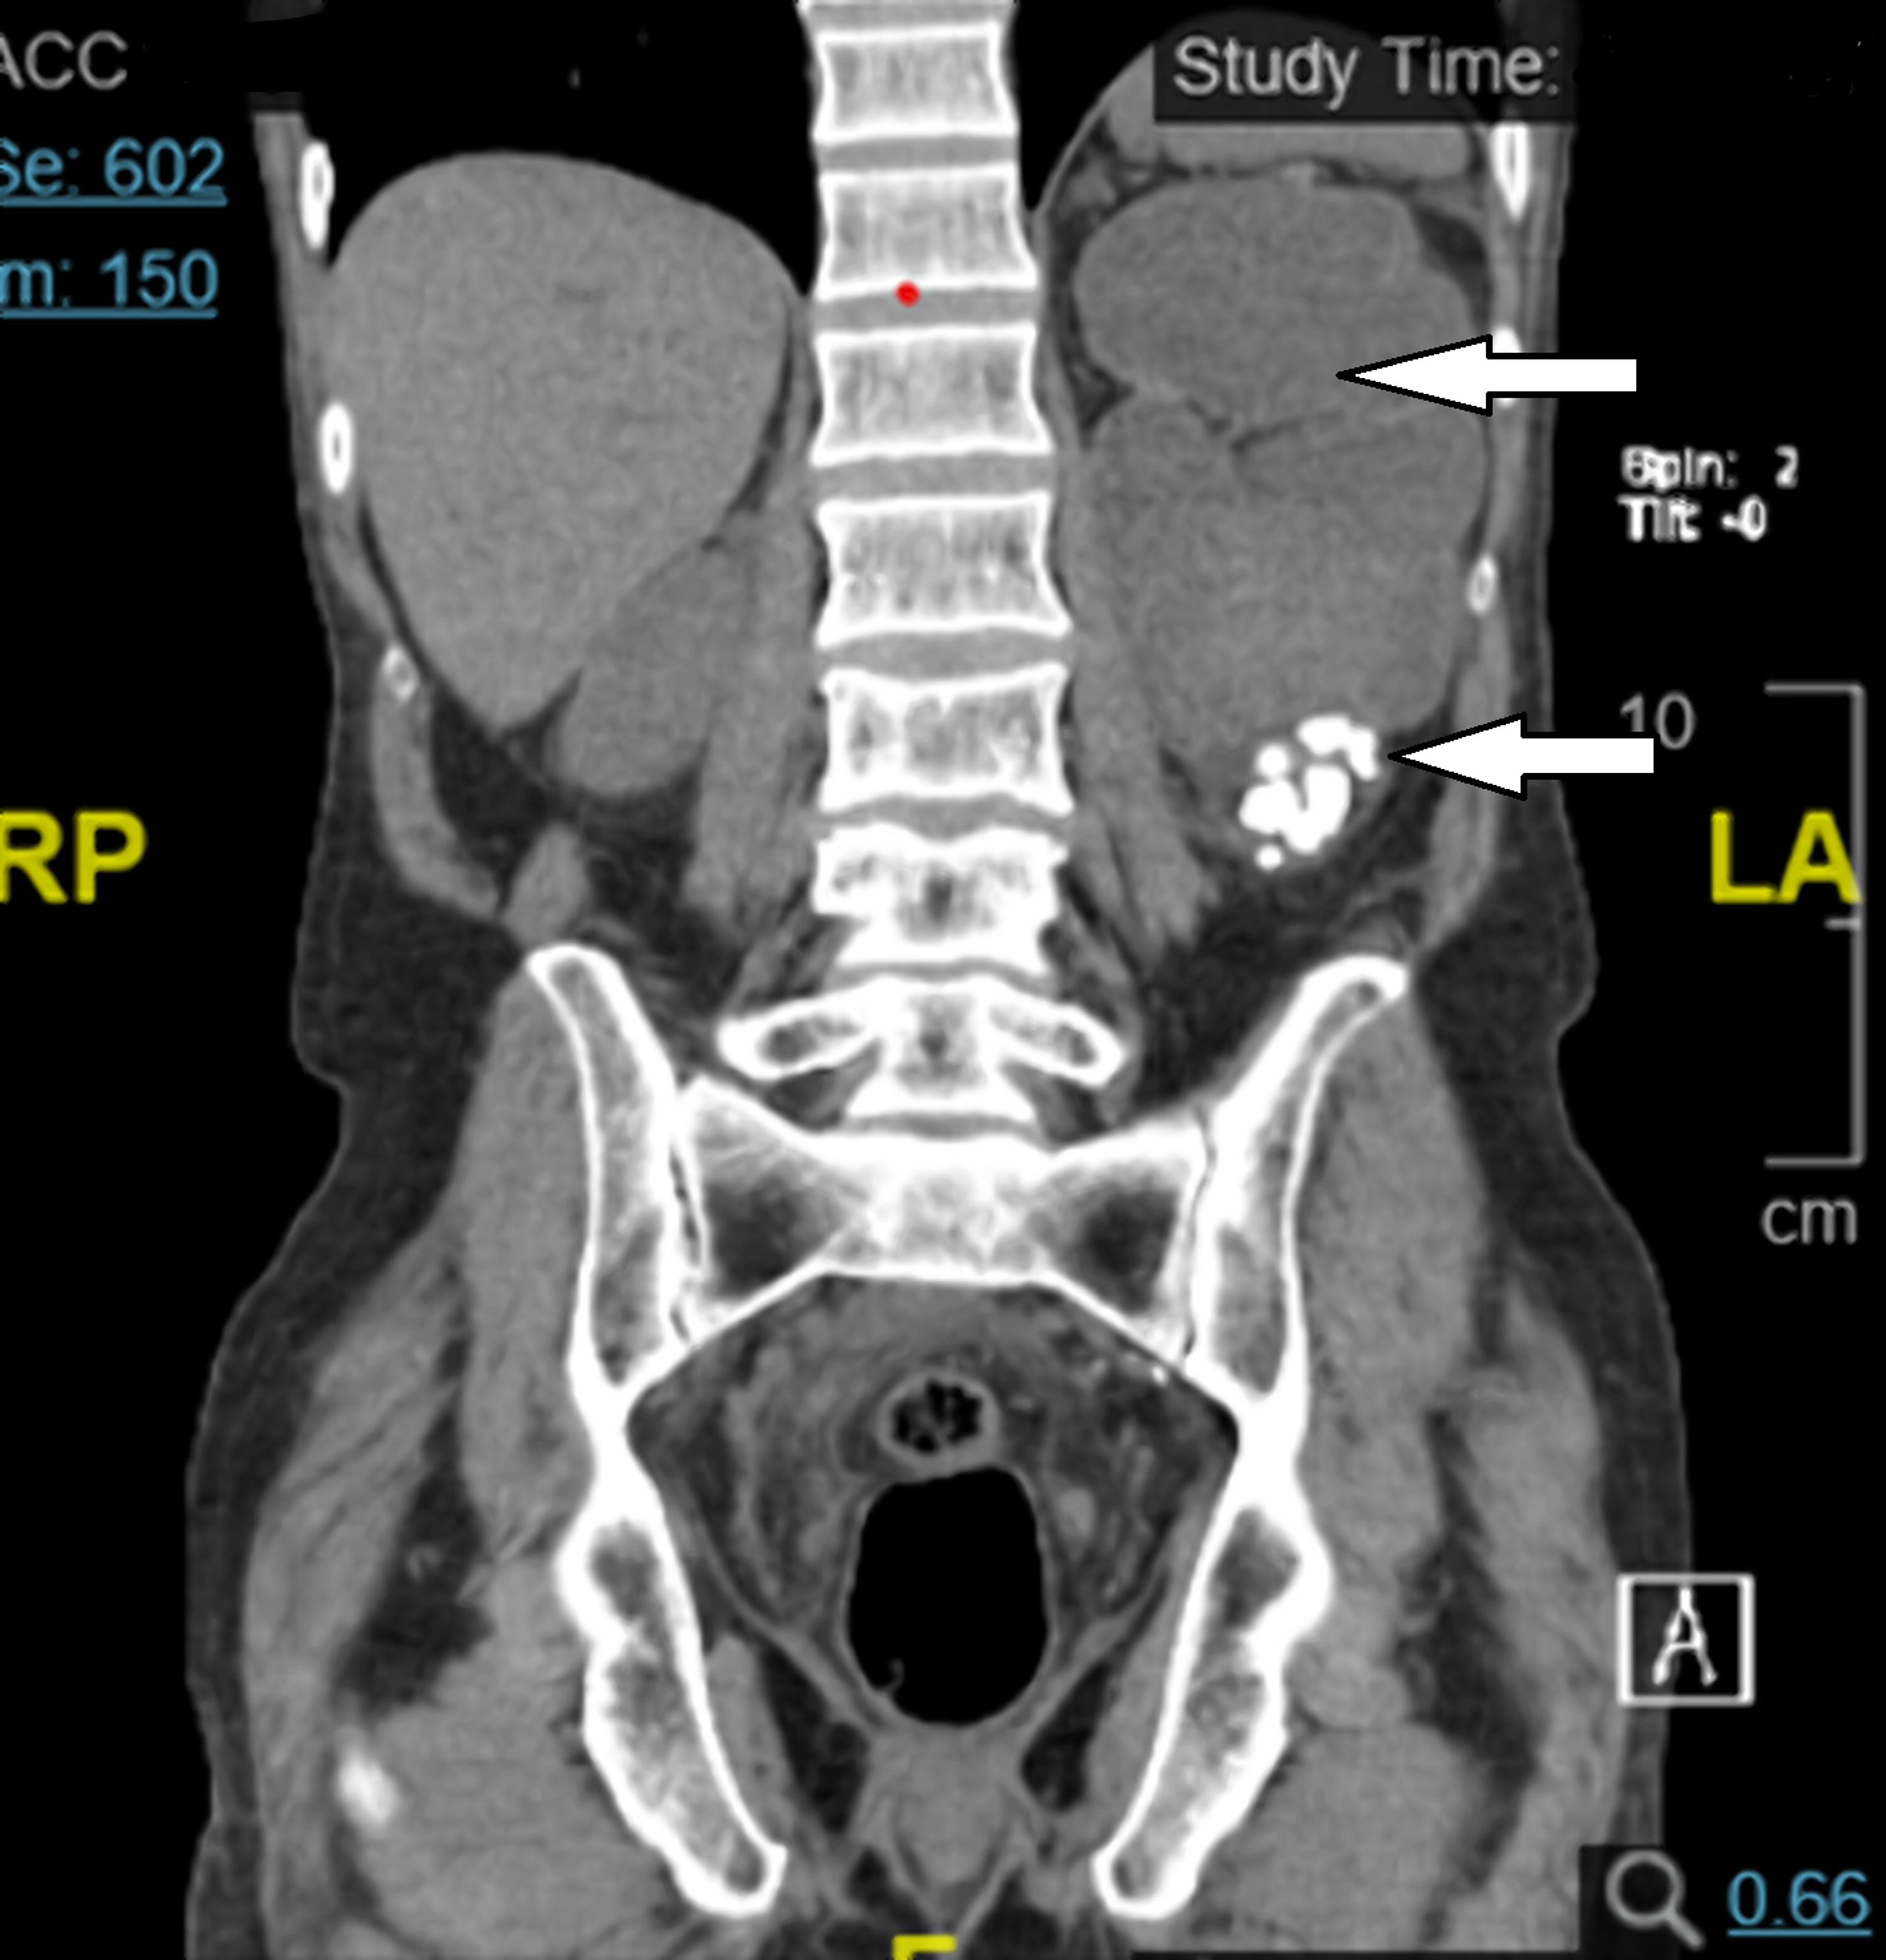

Horseshoe kidney with retrocaval ureter in a 35yearold man with right... Download Scientific Horseshoe Kidney Variants Horseshoe kidney (renal fusion) is when a person is born with the kidneys fused together. Horseshoe kidneys appear as two renal masses located lower in the abdomen than usual, connected by an isthmus of renal tissue. Horseshoe kidneys are the most common fusion defect of the kidneys occurring in approximately 1:500 individuals. A horseshoe kidney is a congenital condition that. Horseshoe Kidney Variants.

Horseshoe kidney with retrocaval ureter in a 35yearold man with right... Download Scientific Horseshoe Kidney Variants A horseshoe kidney is a congenital condition that causes the kidneys to join and form a horseshoe shape. While each child may experience symptoms differently, the most common symptoms of horseshoe kidney include: Horseshoe kidneys are the most common fusion defect of the kidneys occurring in approximately 1:500 individuals. Horseshoe kidney (hsk) is the most common renal fusion, which is. Horseshoe Kidney Variants.